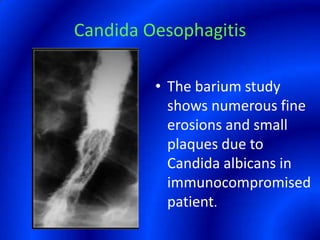

This document provides information about a barium swallow procedure. It begins with an introduction and overview of the embryology and anatomy of the pharynx and esophagus. It then describes the procedure itself, including preparation, technique, views obtained, and indications. Specific conditions that may be examined include pharyngeal and esophageal webs, foreign body impaction, scleroderma, dysphagia, mediastinal masses, and carcinoma. Diagrams are provided to illustrate normal anatomy and various pathological findings.